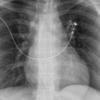

Blunt Chest Trauma

Pneumothorax

Album: Pneumothorax